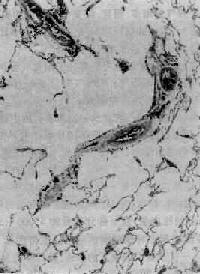

图9-12 腺泡中央型肺气肿 呼吸细支气管呈囊状扩张,伴行肺动脉(径80μm)管壁增厚,其分支内膜增厚,管腔极度狭窄